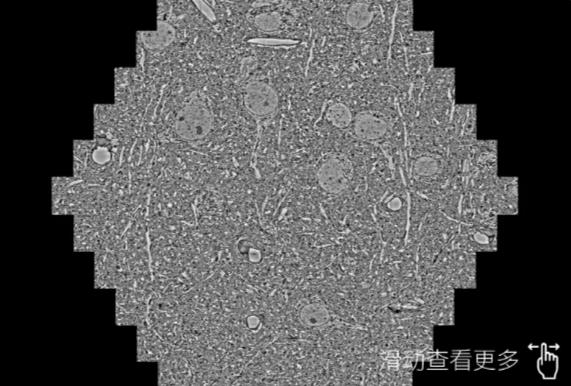

鼠脑切片。左图使用泸州蔡司泸州扫描电镜MultiSEM706对165μmx143pm面积区域成像,耗时仅需1.5秒。右图为鼠脑切片中30μm区域放大效果。样品由芝加哥大学B.Kasthuri提供。

使用蔡司高速泸州扫描电镜MultiSEM对1mm²人脑皮层组织进行高分辨成像,并对其中的各种细胞结构进行三维重构分析。左图展示了2x3mm²组织平面中锥体神经元的三维重构效果。右图显示了局部体积神经元三维重构。图像由哈佛大学chtman实验室提供,渲染图由D. Berger 制作。